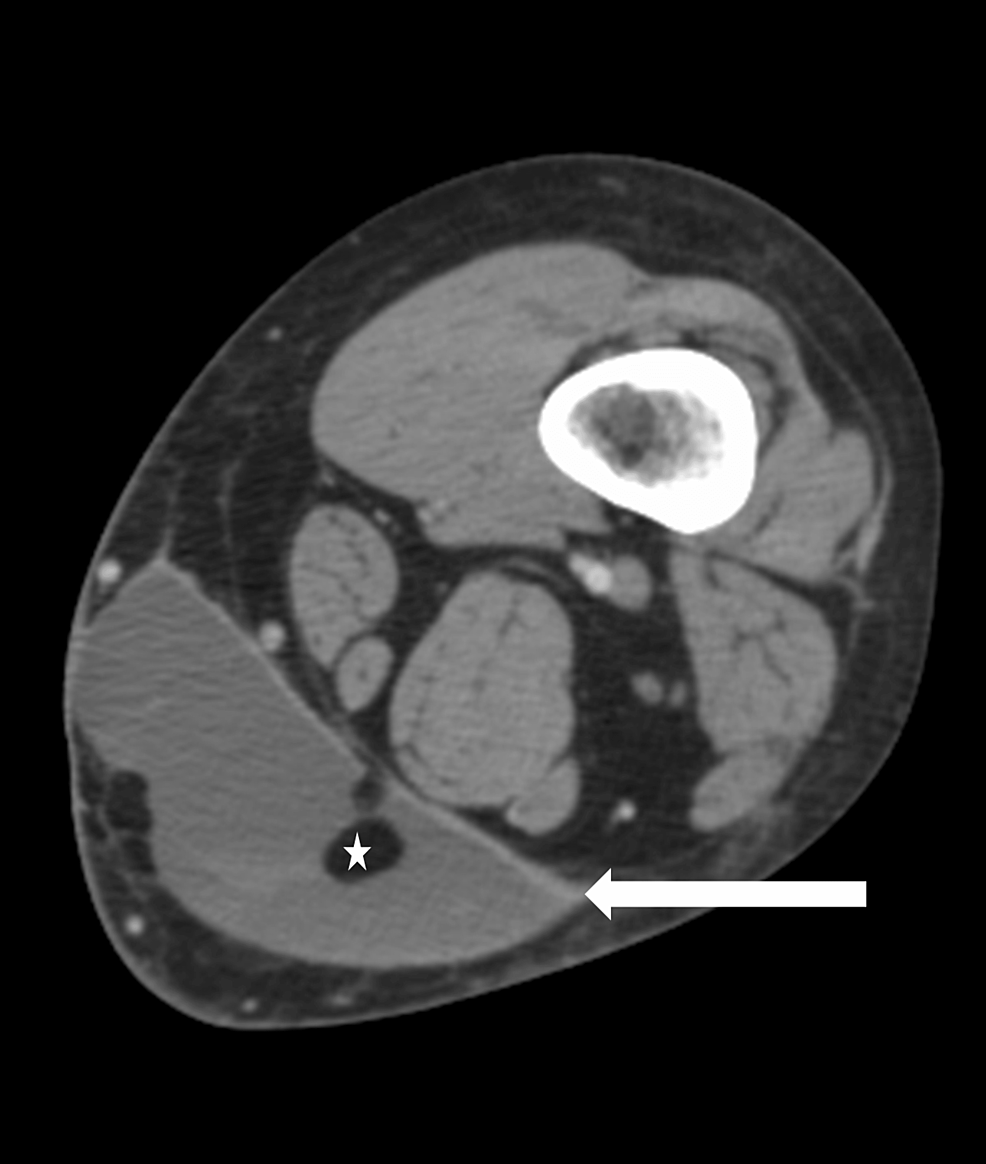

MorelLavallée lesion left hip Image Morel-Lavallee Internal Degloving Injury The thigh, hip, and pelvic region. Morel‐lavallée lesion is a closed soft tissue degloving injury caused by high‐energy violence, usually associated with underlying. Morel-Lavallee Internal Degloving Injury.

A Morel Lavallée lesion represents a closed degloving injury associated with severe trauma which Morel-Lavallee Internal Degloving Injury Morel‐lavallée lesion is a closed soft tissue degloving injury caused by high‐energy violence, usually associated with underlying. The thigh, hip, and pelvic region. Morel-Lavallee Internal Degloving Injury.